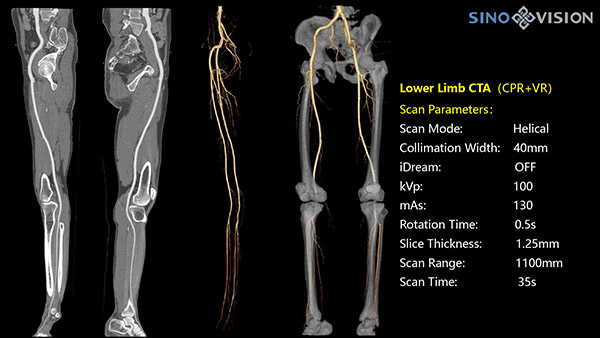

Инновационный 128-срезовый компьютерный томограф SinoVision InsitumCT 568 – это сочетание высокой скорости работы, низкой дозы и максимума возможностей для подавляющего большинства клинических случаев, как в рутинных, так и в углубленных специализированных исследованиях, в том числе педиатрические и кардиологические исследования при сверхнизких дозах.

РМК

Полнофункциональный 128-резовый компьютерный томограф InsitumCT 568 - это лучшее в новом поколении широкодиапазонных томографов с 128 срезами и большой диафрагмой. Этот КТ-сканер с большой апертурой обеспечивает 128 срезов КТ с диафрагмой 76 см, улучшает разрешение изображения до 21Lp/cm, помогает точно диагностировать и лечить заболевания, а также значительно улучшает клинические характеристики и расширяемость оборудования. Позволяет реализовать визуализацию в высоком разрешении и в малых дозах лучевой нагрузки.

Полнофункциональная платформа клинической диагностики может точно определять местонахождение и диагностировать общие повреждения качественно и количественно, а также достигать полнофункциональных клинических показателей, включая обширные кардиологические исследования со сверхнизкими дозами лучевой нагрузки.

- Общий анализа сосудов на основе серии данных КТ